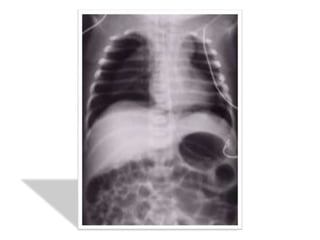

LA RX STANDARD DU THORAX

pleurale

• Décollement partiel avec angle de

raccordement aigu à la paroi ou présence de

brides sous forme de bande opaque

• On a une hyperclarté homogène périphérique

en croissant dépourvue de trame pulmonaire

• Si l’épanchement gazeux est minime on peut

avoir une fine bande claire et un « trapping »

cad une zone d’air du décollement qui ne se

vide pas à l’expiration forcée

• Bride rattachant le poumon à la paroi(risque

de rupture et d’hémothorax)